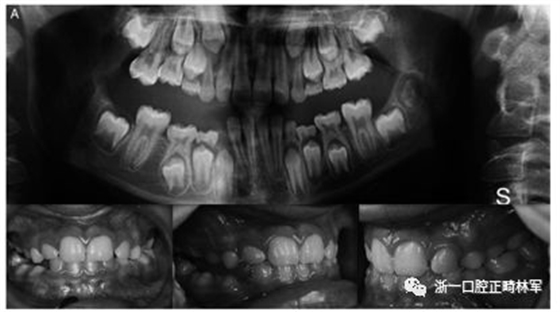

29例中有8例在PTH1R基因中发现杂合致病变异。表2显示了本研究中确定的突变概况。简言之,在8个受影响的受试者中有5个鉴定出三种错义突变,这些受试者以前没有根据与已发表的数据库的比较(表3)进行描述。在两个兄弟中鉴定出CTCF结合位点的变体(c.313×32 A.G rs113566258 SNP)(图1A,B)。

图1.(A,B)两兄弟的口内照片。全景:外显子5的下游变体(CTCF结合位点)rs113566258 SNPc.313±32A>G; 在外显子16中的变体(位置3:46903467)c.1593-95 Del C,p.531 / 532; 外显子10中的同义变体(位置3:46899419)c.1152 G>A.

兄弟姐妹被诊断为I型PFE并显示双边呈现。该变体(PTH1R基因的外显子5的下游c.313×32 A.G)发生在与转录因子相互作用的调节区中。除了这种突变之外,这些兄弟还受到第二个突变的影响,这些突变对每一个都是独特的:一个兄弟姐妹(II:1)也存在在外显子16的基因氨基末端发生的移码缺失,c.1593DelC ,第(Pro532Leufs *)(图1A,B)。

在另一个同胞(II:3)中,鉴定出在蛋白质氨基酸序列水平不引起变异的外显子,c.1152GA(rs200475872;图1A,B)中的同义变体,但涉及改变含氮碱。基于计算机分析,这种改变可能会影响mRNA的折叠并影响其半衰期和蛋白质生产。在这个患者样本中,在一个孤立的病例中发现了同样的同义变体c.1152G.A,由于PFE而具有严重的开合(图2)。

本研究中确定的低咬合的临床特征与PFE基于基因诊断和萌出障碍诊断标准的应用相一致。对特定相关牙科特征的仔细临床检查包括以下内容:至少一颗牙包括低咬合,局限于后部区域,单侧(38%;图1A)和双侧呈现(35%;图1B和2),至少有一个暂时性后牙(48%暂时;图1A,B和3A; 55%永久性,图3B)。

此外,观察到牙面特征如下:由于受影响侧的侧向开放咬伤的严重程度而引起的垂直骨骼不对称(35%;图1A,B和图3A,B);由下颌骨侧向偏离组成的面部不对称(图1A,B和图2;表4)。

这种不对称在单侧开合患者中更为明显。进一步发现受影响的患者与先前报道的患者存在上颌骨收缩和III类牙齿/骨骼关系(28%;图1A,B和图2)。至少有一例患者出现了相对于9名患者的低咬合。表4总结了PTH1R的表型结果和相关的突变分析(N = 8)。